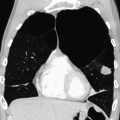

A chest X-ray and complete blood count may be useful to exclude other conditions at the time of diagnosis.[61] Characteristic signs on X-ray are overexpanded lungs, a flattened diaphragm, increased retrosternal airspace, and bullae while it can help exclude other lung diseases, such as pneumonia, pulmonary edema or a pneumothorax.[62] A high-resolution computed tomography scan of the chest may show the distribution of emphysema throughout the lungs and can also be useful to exclude other lung diseases.[15] Unless surgery is planned, however, this rarely affects management.[15] An analysis of arterial blood is used to determine the need for oxygen; this is recommended in those with an FEV1 less than 35% predicted, those with a peripheral oxygen saturation of less than 92% and those with symptoms of congestive heart failure.[14] In areas of the world where alpha-1 antitrypsin deficiency is common, people with COPD (particularly those below the age of 45 and with emphysema affecting the lower parts of the lungs) should be considered for testing.[14]

A severe case of bullous emphysema

Axial CT image of the lung of a person with end-stage bullous emphysema.